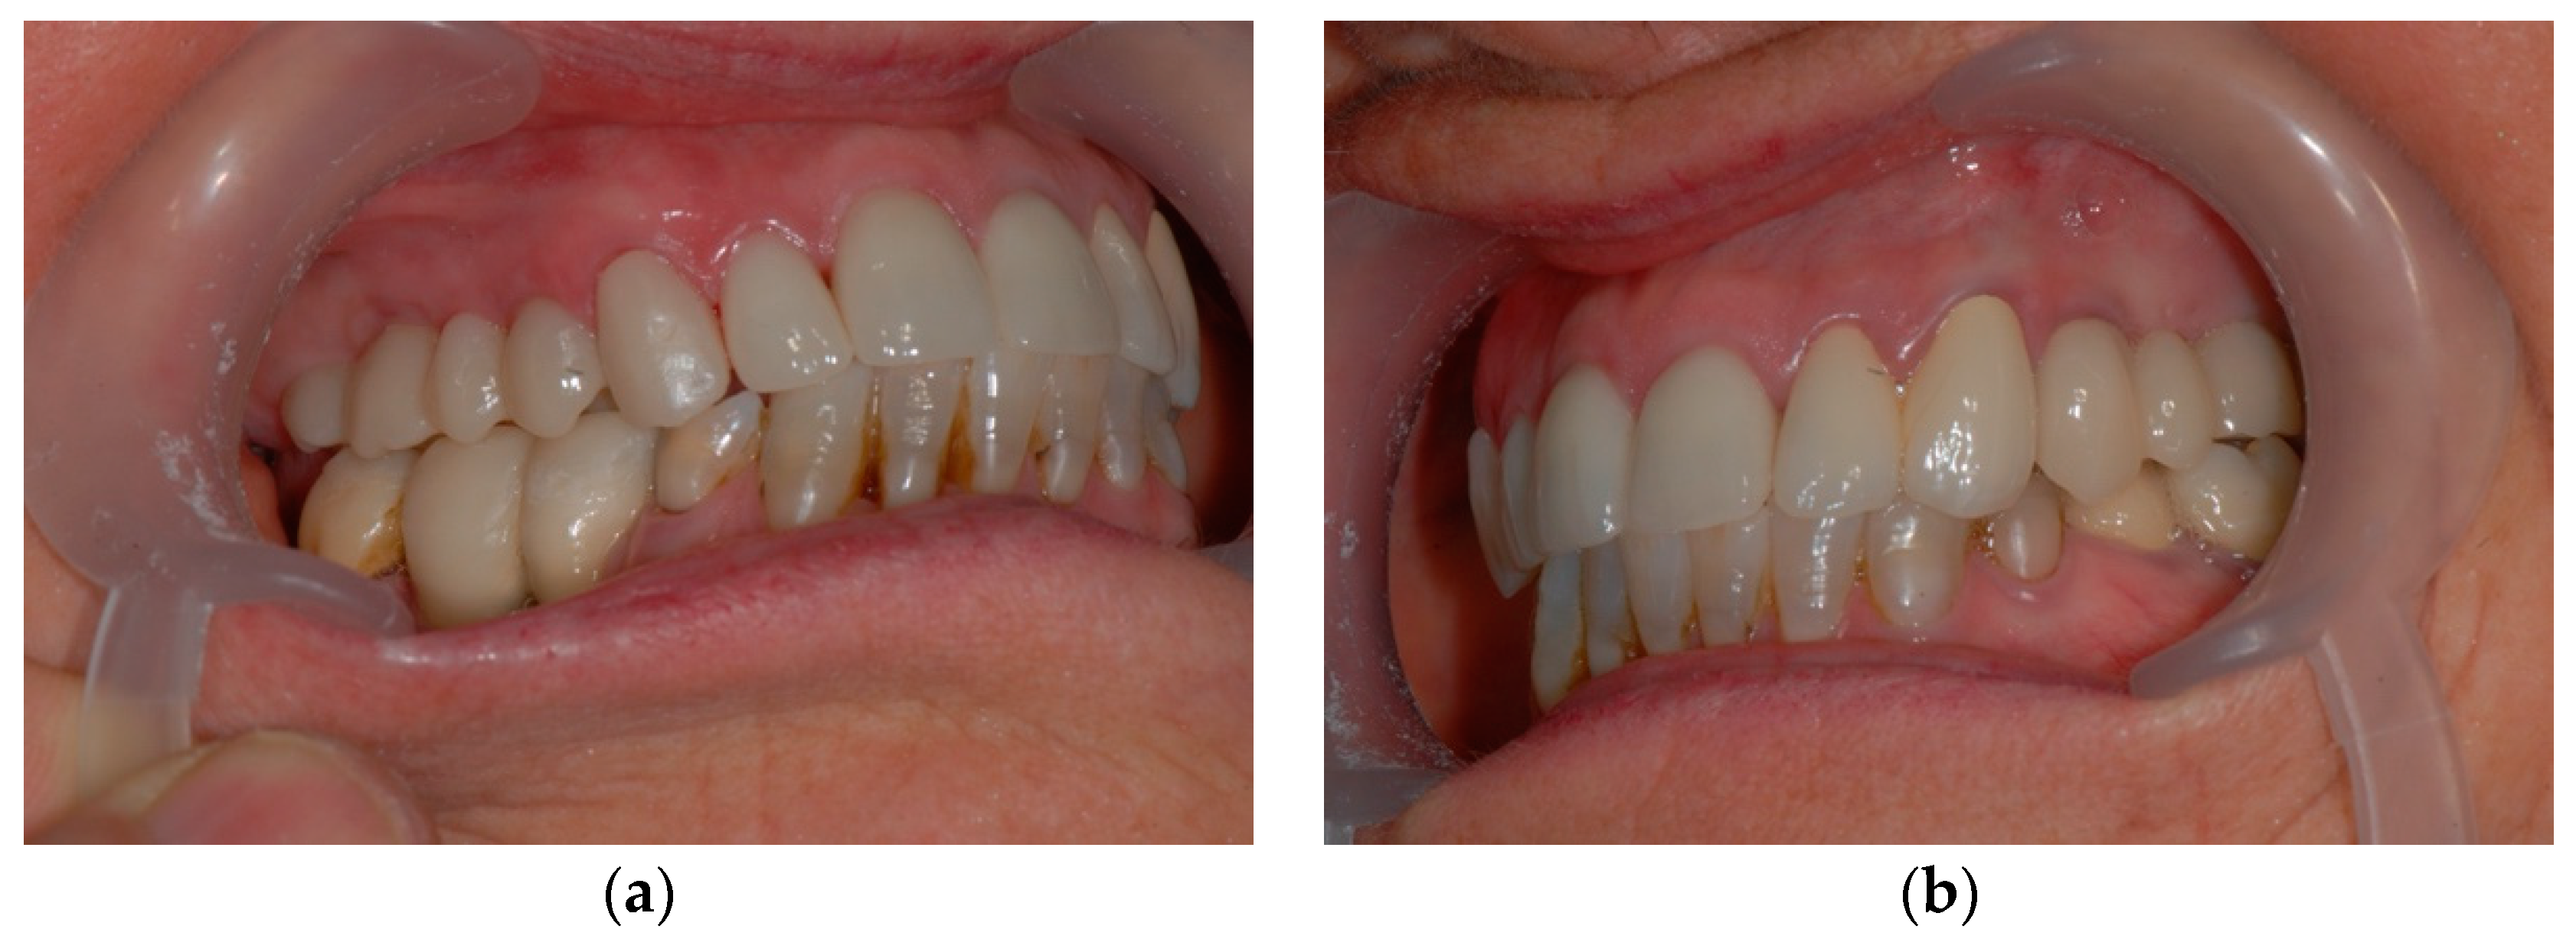

2.6. Case Study